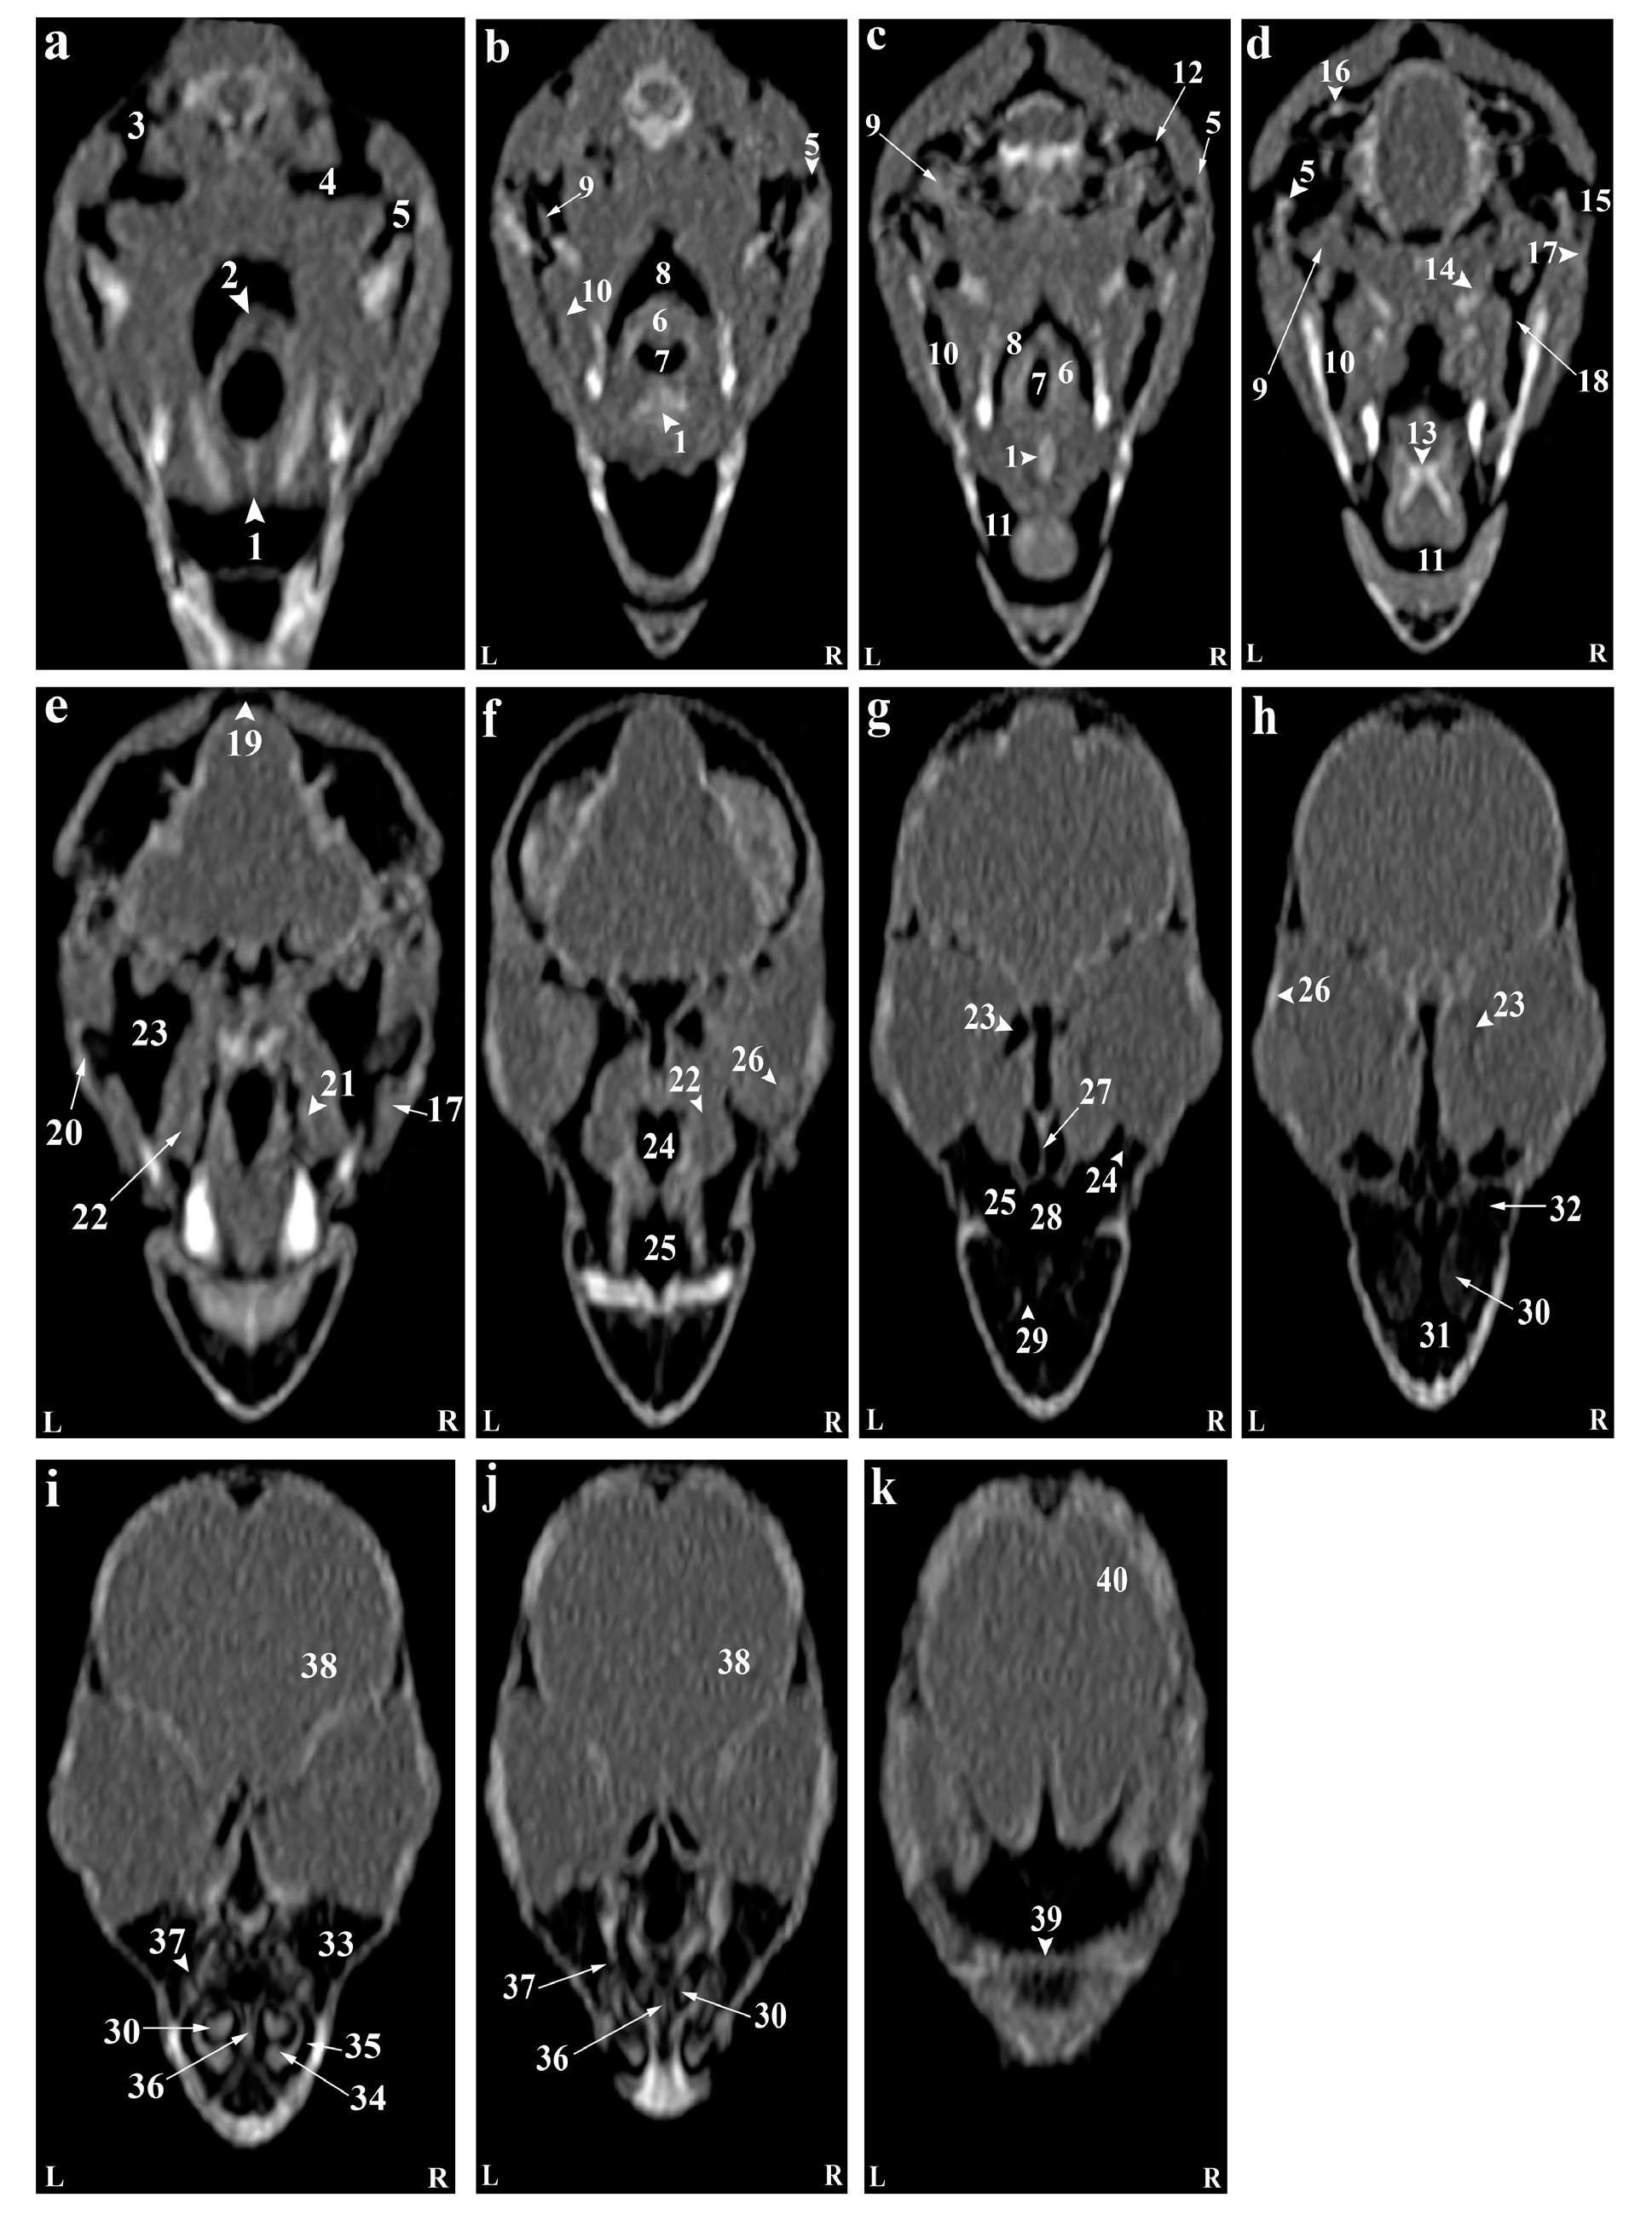

Reconstructed CT images revealed that most structures of the head of the Rose-ringed parakeet (Psittacula krameri) were identifiable. In the 3D images, the parrot's head appeared rounded and compact. The jugal arch and the palatine bone were fused in the remaining parts of the skull, except for the cranial facial bones. Even small bones of the head, such as ear bones and entoglossal bones inside the mouth, could also be evaluated in these CT images. Using the lung window filter, it was possible to observe the bony trabecular in the head. This setting also enabled evaluation of the parietal and temporal bones, nasal conchae, epithelial membranes, the external ear canal, and bony labyrinth. Further, with covering tissues, different parts of the infraorbital sinus could be observed using this filter. Furthermore, different soft tissue windows were adjusted to allow for the identification of brain hemispheres, the cerebellum, optic nerve, pupil muscles, and eye lenses (Figures 2-3). Based on the findings, the columella ossicle, its external cartilage, and the cochlea were not detectable on CT. The eyeballs of all parrots were complete and bony and located on the skull's lateral side (Figure 2i). The mandible appeared bony and lacked a distinct symphysis (Figures 2b and 3a), while the rostrum was keratinous, large, and ventrally curved. The operculum was observed on the dorsal base of the nostrils. Bones such as occipital, maxillary, premaxillary, mandible, palatine, pterygoid, and quadrate were pneumonized and had air bubbles. The nasal cavities were divided by a septum, which thickened slightly from the rostral to the caudal side. Its caudal third was cartilaginous, while the middle third and the rostral were bony. The ectethmoid, mesethmoid, maxillary, and preimaxillary bones were involved in the formation of the nasal cavity, and the nasal cavity comprised three parts: olfactory, respiratory, and vestibular. Each nasal cavity had a single duct with caudal, middle, and rostral cartilaginous conchae. The rostral concha C-shaped and located in the vestibular part of the nasal cavity decreased in thickness from the rostral to the caudal direction and contained a basal lamella along the lateral nasal cavity wall. The middle concha was in the form of long ducts that originated from a basal lamella and was located in the upper respiratory tract of the nasal cavity. This lamella also splits into a sinusoidal and a spiral lamella. The spiral lamella extended to the entrance of the nasopharyngeal canal. The caudal concha, smaller and hollow, was located at the nasal cavity's rear. The nasal and oral cavities were connected through the nasopharyngeal canal (Figures 3c and 4h), which connected the maxilla-palatal process and the palatine bone's choanal part from the rostro-lateral and caudal sides. The caudal part of this duct linked with the interorbital septum (Figures 3e and 4f). The oral cavity included the palatal, mandible, premaxillary, and maxillary bones, along with associated muscles and tongue. These bones, along with the pterygoid, contributed to pharynx formation (Figures 4c-d). The choana was located in the dorsal part of the pharynx and oral cavity and connected the oral cavity to the nasal cavity (Figures 2g). The tongue was strong and large, and could be identified in the CT images, located in the middle third and caudal of the inferior part of the oral cavity (Figures 2c-d). The oral cavity had a hyobranchial apparatus. The tongue's base was in close contact with the paraglossum and the cranial part of the basihyal. Bishyal processes and uhorial bones were detectable in the trachea's larynx and cranial part. The branchial horn (caudal part of the hyobranchial apparatus) was located in the inner part of mandible's ramus, or tracheal cranial part. Its caudal third was associated with mandible masseter muscles. The larynx consisted of a ring-shaped cricoid cartilage and two pyramid-shaped arytenoid cartilages. The results of the current study demonstrated that the procricoid cartilage was located within the middle part of the cricoid cartilage and formed the larynx 's dorsocaudal part (Figures 2b-j). The glottis was centrally placed in the larynx and surrounded by arytenoid cartilages. While laryngeal mounds (Mons laryngealis) were visible in CT cross-sectional. The place where the cricoid joins the tracheal cartilages also appeared ring-shaped in these images (Figures 2f and 4f).

Figure 2. Representative photographs of anatomic cross sections of the adult cockatiel (Nymphicus hollandicus) head. A (level of the Eye) and B (level of the external acoustic meatus) in the dorsal plane and C (level of the rostral border of the orbital fossa) and D (level of the external acoustic meatus) in the transverse plane. A: (1) Ramphoteca, (2) Premaxilla bone, (3) Maxilla bone, (4) Left nasal cavity, (5) Caudal nasal concha, (6) Infraorbital sinus, (7) Eye, (8) Brain hemispheres, (9) Falx cerebri, (10) Occipital bone, (11) Temporal bone. B: (1) Ramphoteca, (2) Premaxilla bone, (3) Palatine bone, (4) Ethmomandibularis muscle, (5) Pterygoideus muscle, (6) Cerebellum, (7) Bony labyrinth, (8) External acoustic meatus, (9) Caudal nasal concha, (10) Occipital bone. C: (1) Fronto-parietal bone, (2) Eye, (3) Infraoebital sinus, (4) Pterygoideus muscle, (5) Ethmomandibularis muscle, (6) Hard Palate, (7) Eye, (8) Caudal nasal concha, (9) Lingual process of hyoid bone, (10) tongue, (11) Choanal cleft, (12) Mandible. D: (1) Cerebrum, (2) Falx cerebri, (3) Occipital bone, (4) Brain stem, (5) Chiasma optic, (6) External acoustic meatus, (7) Ethmomandibularis muscle, (8) Pterygoideus muscle, (9) Mandible, (10) Hard palate, (11) Lingual process of hyoid bone. R, Right; L, Left.

Figure 3. (a-n) Transverse computed tomography reconstruction images in the lateral plane of the normal skull of the cockatiel (Nymphicus hollandicus). (1) Rostral diverticulum septum, (2) Premaxillary bone, (3) Rostral diverticulum, (4) Paraglossum, (5) Bony part of nasal septum, (6) Mandible bone (pneumonized), (7) Palate bone opening, (8) Rostral nasal concha, (9) Transverse canal, (10) Maxillary process of palatal bone, (11) Tongue, (12) Middle nasal turbinate, (13) Basal layer of middle nasal turbinate, (14) Nasal cavity, (15) Cartilaginous part of nasal septum, (16) Nasopharyngeal airway, (17) Lateral border of palatine bone, (18) Periorbital process of infraorbital sinus, (19) Jugal part of infraorbital sinus, (20) Jugal arch, (21) Glottis, (22) Laryngeal protrusion, (23) Arytenoid cartilages, (24) Bronchial horn, (25) Trachea, (26) Choana of palatal bone, (27) Ethmomandibular muscle, (28) Periorbital part of the infraorbital sinus, (29) Caudal nasal turbinate, (30) Infraorbital sinus foramen, (31) Infraorbital part of the infraorbital sinus, (32) Eyeball, (33) Epithelial membrane, (34) Tracheal cartilage ring, (35) Infraorbital septum, (36) Cricoid cartilage, (37) Procricoid cartilage, (38) Scleral ossicles, (39) Suborbital arch, (40) Frontal bone (pneumonized), (41) Pterygoid and quadrate muscles, (42) Larynx, (43) Zygomatic process of the squamosal bone, (44) Quadrate bone (pneumatized), (45) Quadrature part of infraorbital sinus, (46) Postorbital part of infraorbital sinus, (47) External acoustic meatus, (48) Cervicocephalic diverticulum, (49) Brain stem, (50) Bony labyrinth. L, Left; R, Right.

Figure 4. (a-f) Sagittal computed tomography reconstruction images (lateromedial plane) of the normal skull of the cockatiel (Nymphicus hollandicus). (1) Scleral bones, (2) Suborbital arch, (3) Postorbital part of the infraorbital sinus, (4) Quadrate bone (pneumonized), (5) External ear foramen, (6) Mandible bone, (7) Cervicocephalic diverticulum, (8) Occipital bones (pneumonized), (9) Infraorbital part of infraorbital sinus, (10) Periorbital process, (11) Epithelial membrane, (12) Jugal portion of infraorbital sinus, (13) Cervical vertebrae, (14) Trachea, (15) Encephalon of the brain, (16) Caudal nasal turbinate, (17) Middle nasal turbinate, (18) Rostral nasal turbinate, (19) Transverse canal, (20) Premaxillary bone (pneumonized), (21) Palate bone (pneumonized), (22) Rostral diverticulum, (23) Frontal bone (pneumonized), (24) Nasal cavity, (25) Nasopharyngeal airway, (26) Larynx, (27) Paraglossum, (28) Basihyal, (29) Bony part of nasal septum, (30) Infraorbital septum, (31) Nostril, (32) Tracheal rings, (33) Cartilaginous part of nasal septum, (34) Tongue. Ca, Caudal; Cr, Cranial.

The entire pupil cavity was filled with an oval eyeball bordered externally by the frontal bone and suborbital arch. A bony trabecular septum separated the pupils. All parrots under study had a complete bony eyeball (Figures 2j and 4h). In the obtained CT images, the eye lens was not clearly detectable, and the cranial chamber (aqueous) and the caudal (vitreous) were not distinguishable. The retina was unrecognizable. Eyeball muscles, lacrimal glands, and the third eyelid (nictitating membrane) had similar attenuation values and were indistinguishable. Scleral bones appeared as two indistinct lines on cross-sections images and as circular or round in sagittal images (Figures 2j,3a and Figures 4h).

The parakeet's encephalon could be evaluated in the CT images (Figures 3c and 4i). Although, brain hemispheres such as the telencephalon and diencephalon, along with the brainstem and cerebellum, were well identified and could be distinguished from each other in cadavers, they shared similar attenuation in CT, making them difficult to differentiate. The findings revealed that the external acoustic meatus and the external opening of the ear were recognizable in CT images (Figures 2m and 4c), but the tympanic membrane was not visible in either CT images or carcasses examinations. Hence, different parts of the middle ear were not distinguishable. Nonetheless, the presence of low-resolution lines in the distal third of the external acoustic meatus can demonstrate parts of the middle ear such as infraorbital (columella) and extracolumella cartilage. The bony labyrinth of the inner ear was clearly visible in both in the cadaver samples and CT images.

Based on our findings, the paratympanic sinus could not be identified in CT images. Muscles of the head were only faintly visible hyperattenuated lines. Larger muscles, such as quadrate, pterygoid, and ethmomandibular, were somewhat distinguishable, although the jaw adductor muscle despite its size, was poorly detectable in CT images (Figures 2g and 4c). The infraorbital sinus was surrounded by skull bones and covering and muscular tissues and was found as a large triangular cavity that covered a large part of the head. The premaxillary bone was located in the rostral part of this sinus, with palatine and pterygoid bones located in its inner part. Further, the quadrate, jugal arch, and mandible were located in the lateral part. This sinus included the rostral diverticulum, transverse canal, postorbital, preorbital, infraorbital, quadrate bones, cervicocephalic diverticulum, and mandibular recess. The rostral diverticulum and the transverse canal were single, and the remaining parts were in pairs. Except for the periorbital parts, the transverse canal, and the rostral diverticulum, the remaining parts of the suborbital sinus were covered by the masticatory muscle (Figures 2-4). The rostral diverticulum, extending along the premaxillary bone, was divided into two parts by a thin bony septum, which gradually thinned from rostral to the caudal direction, and eventually disappeared in the middle parts of the diverticulum. The transverse canal was a short and horizontal passage. The maxillary process of the palatine bone and the upper jaw-palatine process (maxillopalatine) of the maxilla, were located in this canal's ventral and distal parts, respectively. This canal connected the periorbital region and rostral diverticulum (Figures 2a,3h and 4h). The nasopharyngeal duct divided the periorbital region into left and right parts. The jugal portion was connected dorsally to the periorbital region, ventrally to the choanal part of the palatine bone, and laterally to the jugal arch. A relatively thin epithelial layer separated the periorbital and the jugal portion. These subdivisions were connected in the caudal part, near the infraorbital part of the infraorbital sinus. The infraorbital part, the largest part, covered a large area of the ventral surface of this sinus and extended to the eyeball. It connected to the palatine bone and interorbital septum from the medial part and to the suborbital and jugal arches from the lateral part. The infraorbital and postorbital parts were directly connected. The infraorbital and postorbital parts were the largest parts of the infraorbital sinus, respectively. The postorbital part was located in the pterygoid's lateral part, the zygomatic process's internal part, and the jugal bow's posterior part, which was connected with the musculature. The masseter, pterygoid, quadrate, and temporal muscles were located in the postorbital area. The caudoventral part of postorbital was connected to the quadrate portion. The smallest part of the infraorbital sinus was related to a quadrate part, which was laterally connected to the quadrate bone. The mandibular recess and cervicocephalic diverticulum were linked to the postorbital part. The mandibular recess was visible in the inner and rostral parts of the mandibular ramus. In fact, this recess was located in the inner part of the postorbital and the ventral part of the infraorbital canal. Lastly, the cervicocephalic diverticulum was detectable and extended to the cervical region (Figures 2n and 3b).